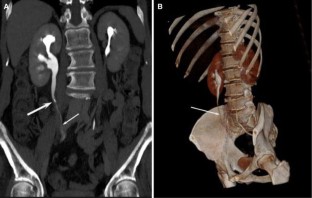

Usefulness of computed tomography performed immediately after excretory urography in patients with delayed opacification or dilated upper urinary tract of unknown cause

To evaluate the diagnostic value of computed tomography (CT) performed immediately after excretory urography (EU) in patients with delayed renal opacification or dilated upper urinary system with nonconclusive diagnosis after EU.

CT was performed immediately after EU in 39 patients with delayed opacification or dilated upper urinary system of unknown cause, without additional intravenous contrast administration for the CT study. We classified EU + CT findings as benign or malignant causes and we compared our results with the final diagnosis.

The combination of EU + CT correctly diagnosed 38 out of the 39 cases with a sensitivity of 97%. Correct diagnosis was established in all malignant cases (n = 17) but one benign case consistent with blood clots in the upper urinary tract was incorrectly diagnosed as a multicentric urothelial carcinoma. Sensitivity, specificity, and accuracy for the diagnosis of the underlying cause with EU + CT was 100%, 95%, and 97%, respectively. The final diagnoses were: urothelial carcinoma (n = 10), stone disease (n = 10), bladder tumor (n = 4), benign post-treatment ureteral stenosis (n = 4), ureteral invasion (n = 3), benign bladder disease (n = 2), urinary tract infections (n = 2), crossing vessels (n = 1), ureteropelvic junction obstruction (n = 1), retrocaval ureter (n = 1), and blood clots in the upper urinary tract due to bleeding renal metastasis from lung cancer (n = 1).

Combined EU and CT study allowed correct diagnosis of the underlying cause of delayed excretion or upper urinary tract dilatation in 97% of cases. The combination of EU and CT provides diagnosis reducing time and radiation.